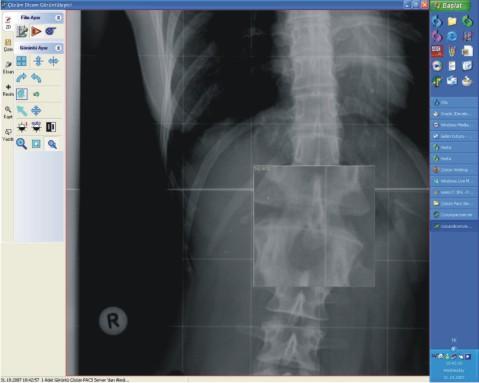

Panaromik görüntüler, çözünürlükleri bozulmadan büyütülerek ayrıntılı bilgiler elde ediliyor.

Çözüm PACS, merkezi veri tabanında bilgilerin depolanması ile oluşan sayısal arşiv (görüntüler üzerinde işlem yapmaya izin verecek şekilde yüksek çözünürlükte saklandığı için ölçüm ve tanıya ilişkin işlemler kolaylıkla yapılabiliyor), bilgilerin yeniden kullanılmasını arşivlenen bilgilerin modern tanı yöntemleri ile incelenmesini sağlıyor.

Sayısal görüntüler üzerinde işlem ve ölçüm yapılabiliyor. Görüntüler ve raporların her an, her yerde (tüm iş istasyonları üzerinden sorgulama yapılarak) ulaşılabilir olmasına ve görüntü işleme ve ölçüm (mesafe, açı, uzunluk, yoğunluk) yapılabilmesine olanak sağlıyor.

Radyoloji uzmanlarının tanı süreçlerinin sonuçlanmasında ve doğruluğunda en büyük yardımcı etken Çözüm PACS oluyor [sayısal olarak elde edilen panoromik görüntüler, çözünürlük bozulmadan büyütülüp, belirli bir noktaya odaklanarak, daha detaylı bilgiler elde ediliyor, görüntülerin herhangi bir yerine yazı veya şekil yerleştirmesi ve seçilen görüntünün fare kontrolünde yer değiştirmesi (pan) ve tam ekran incelemesi mümkün oluyor.] İncelenen görüntüler istenildiğinde DICOM yazıcılara gönderilerek film olarak basılabiliyor.